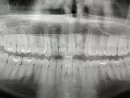

На снимке никаких патологических изменений не отмечено. В случае травматического поражения слизистой рекомендуется проводить антисептическую обработку слизистой (ванночки с "Хлоргексидином", "Фурацилином"), и на пораженный участок наносить противовоспалительный гель ("Холисал", "Метрогил Дента", "Солкосерил").